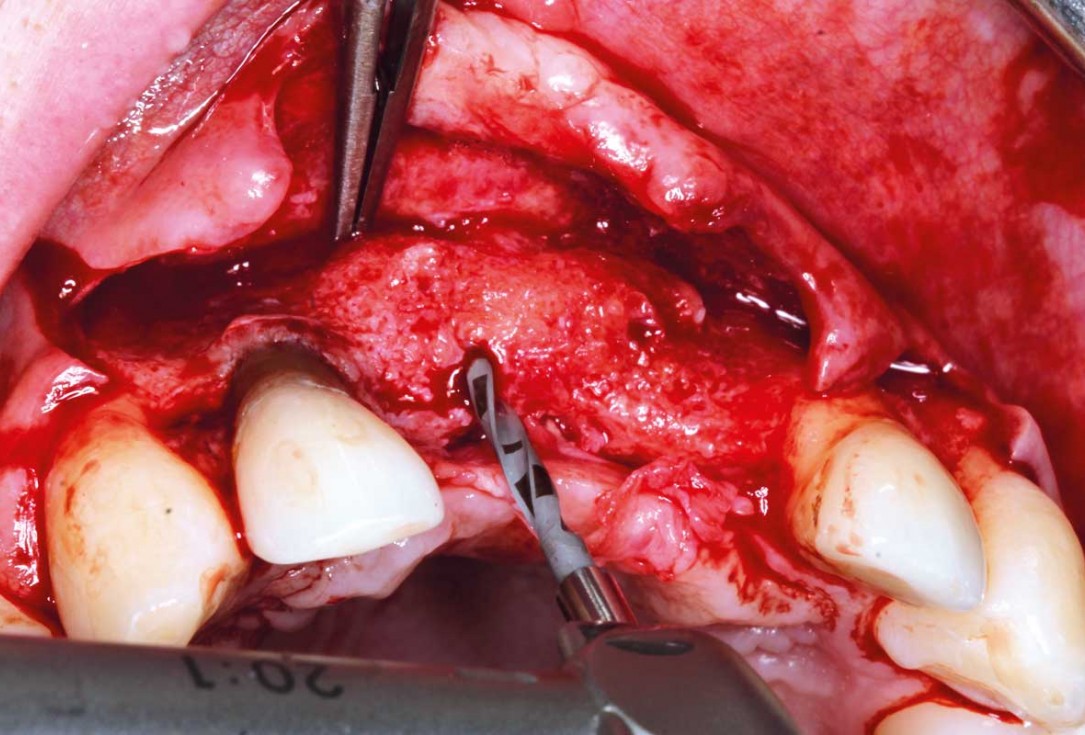

04/26 - Combined vertical and horizontal bone defect in area 21

Ridge augmentation in the maxilla with maxgraft® bonebuilder in the aesthetic zone - Dr. M. Kristensen